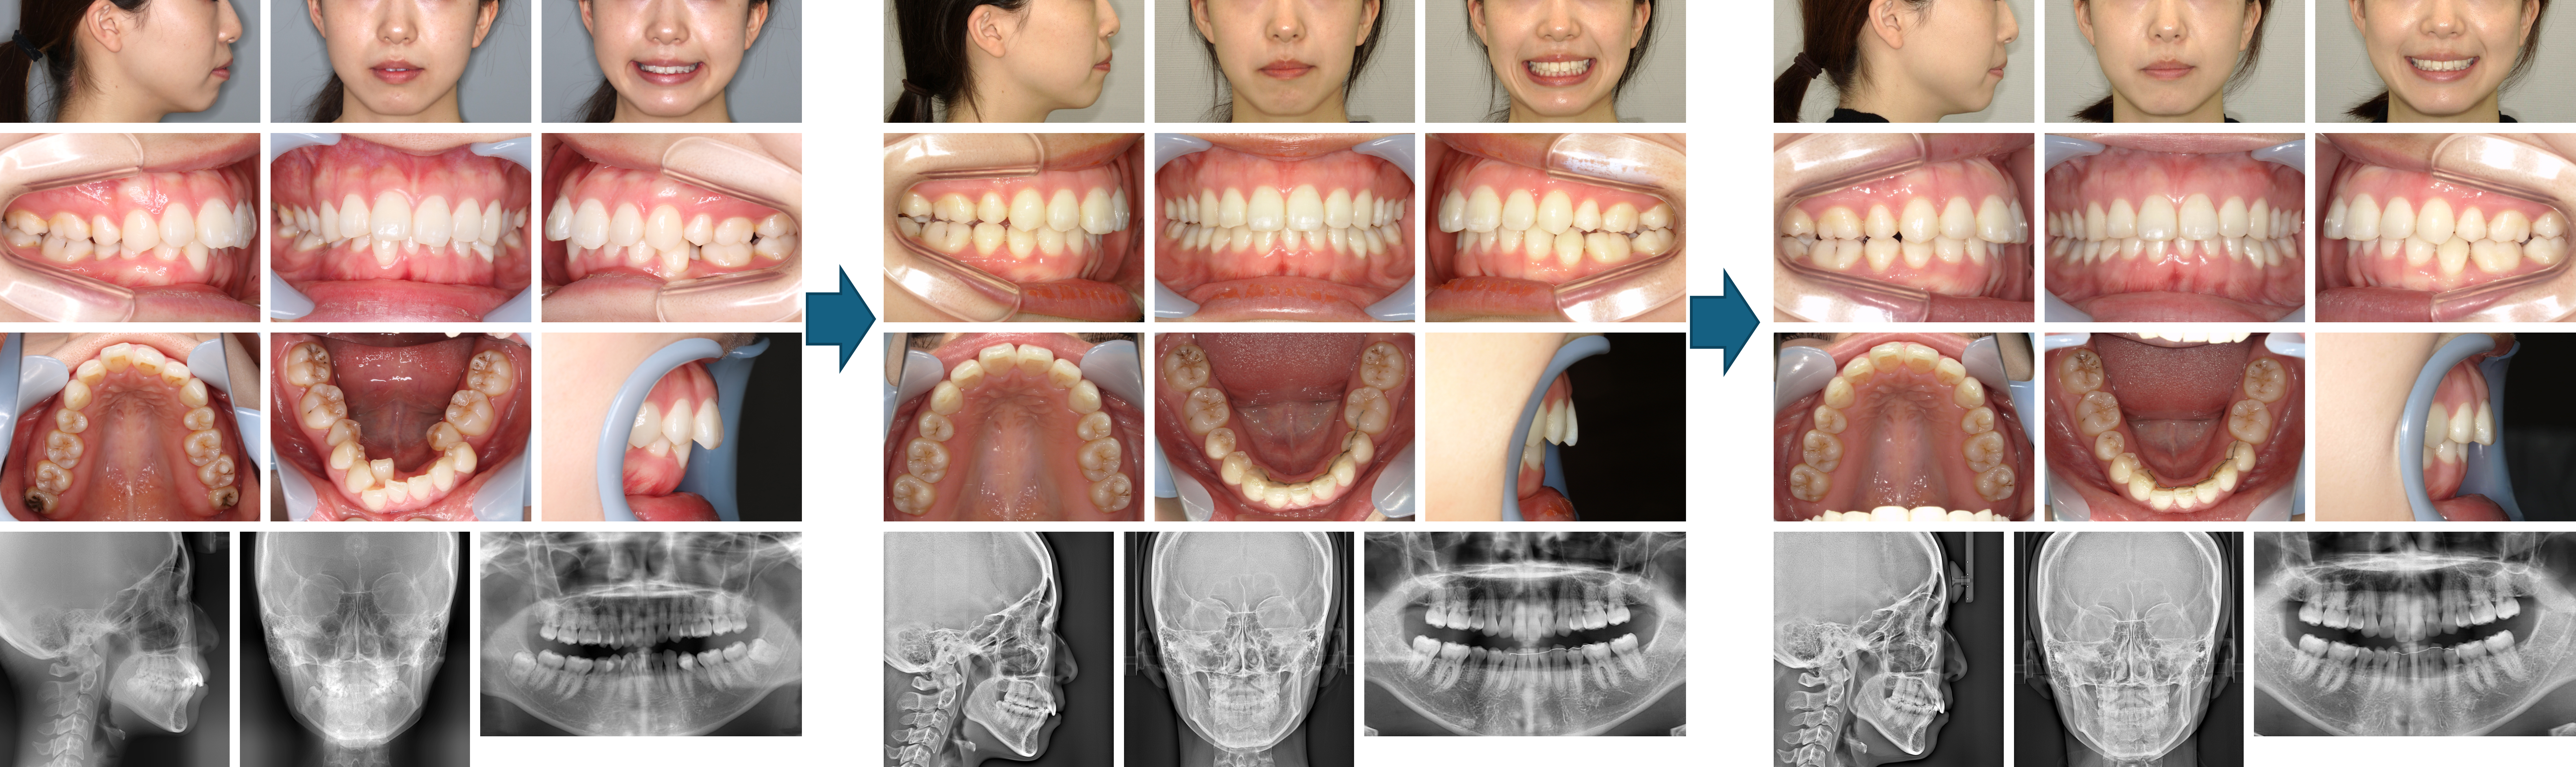

【治療例】初診時年齢:22歳4か月 / 性別:女性 / 主訴:前歯が出ている。もっと笑顔が作れるようになりたい。

症例の概要:この症例は左側上顎中切歯の突出による口唇閉鎖不全を主訴に来院された。上顎の歯列弓はV字歯列弓で上顎前歯部は重なっていたため、上顎両側側切歯を抜歯し上顎前突の改善を図った。その結果、上下歯列の正中線が一致したほか、口唇閉鎖が容易になった。

主訴:前歯が出ている。もっと笑顔が作れるようになりたい。

診断名:上顎V字型歯列弓を伴った上顎前突症例

使用した主な装置:咬合挙上版、マルチブラケット装置

抜歯/非抜歯および抜歯部位:抜歯(上顎両側側切歯)

治療期間:3年5か月

治療回数:45回

リスクの副作用:歯の移動や抜歯による違和感や疼痛、口内炎、歯肉退縮、歯根吸収が生じることがある